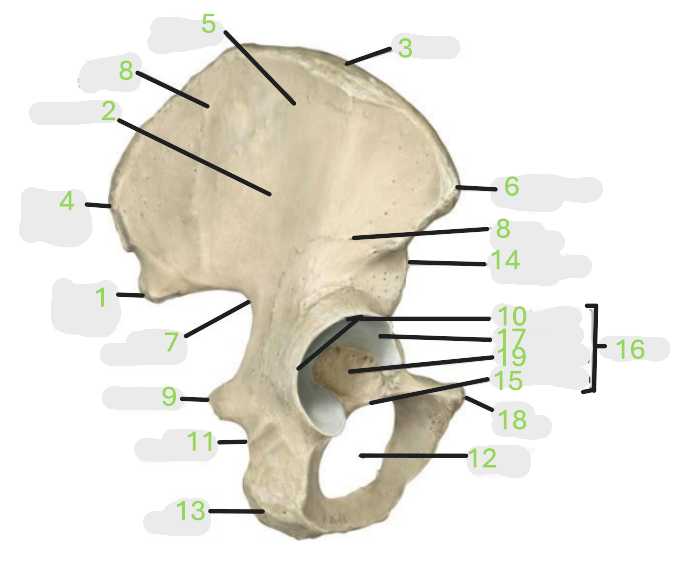

Where is the posterior inferior iliac spine

1

Where is the gluteal surface

2

Where is the iliac crest

3

Where is the posterior superior iliac spine

4

Where is the anterior gluteal line

5

Where is the anterior superior iliac spine

6

Where is the greater sciatic notch

7

Where is the inferior gluteal line

8

Where is the ischial spine

9

Where is the acetabular rim

10

Where is the lesser sciatic notch

11

Where is the obturator foramen

12

Where is the ischial tuberosity

13

Where is the anterior inferior iliac spine

14

Where is the acetabular notch

15

Where is the acetabulum

16

Where is the lunate surface

17

Where is the pubic tubercle

18

Where is the acetabular fossa

19